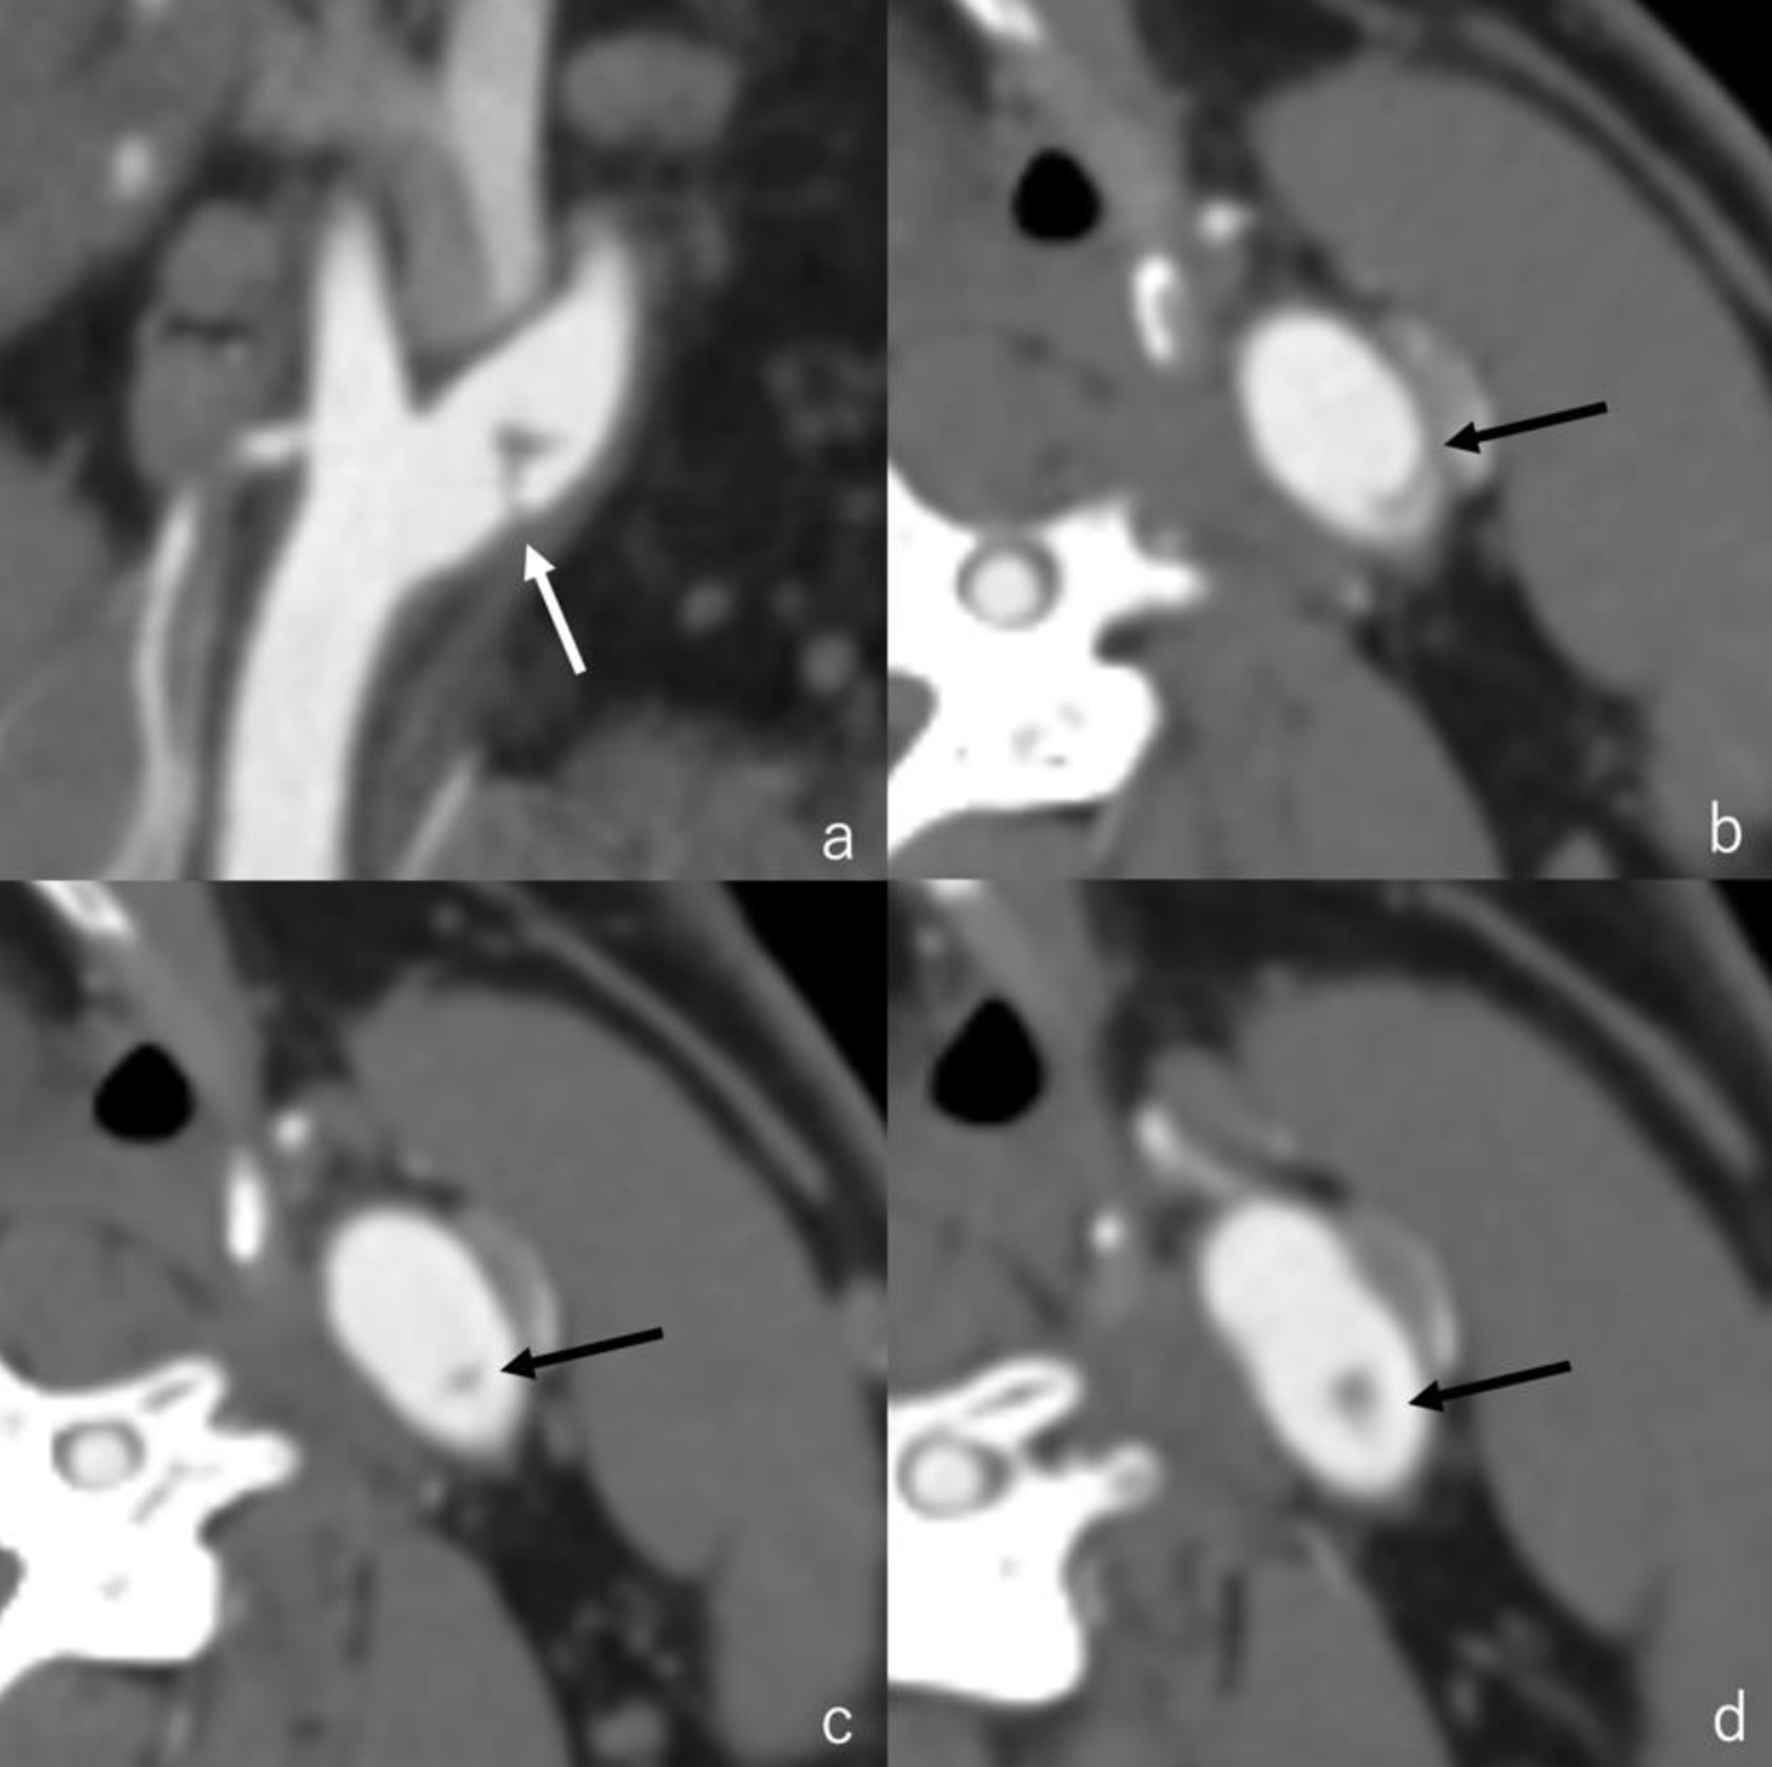

The electrocardiogram showed no evidence of atrial fibrillation. Diffusion-weighted image (DWI) of his head magnetic resonance imaging (MRI) revealed high intensity area of the left middle cerebral artery (MCA) area (Fig. 1a). T2* of his head MRI revealed a low intensity area in the left basal ganglia (Fig. 1b). Head magnetic resonance angiography (MRA) revealed loss of the left MCA (Fig. 1c). Cervical MRA showed no apparent stenosis (Fig. 1d). The patient was hospitalized and treated conservatively. Due to hemorrhage in the left basal ganglia, the patient was treated with edaravon (60 mg/day) without antithrombotic agents.

Click for large image

Figure 1. (a) Diffusion-weighted image of his head MRI revealed high intensity area of the left middle cerebral artery area. (b) T2* of his head MRI revealed a low intensity area in the left basal ganglia. (c) Head MRA revealed loss of the left middle cerebral artery. (d) Cervical MRA showed no apparent stenosis. MRA: magnetic resonance angiography; MRI: magnetic resonance imaging.